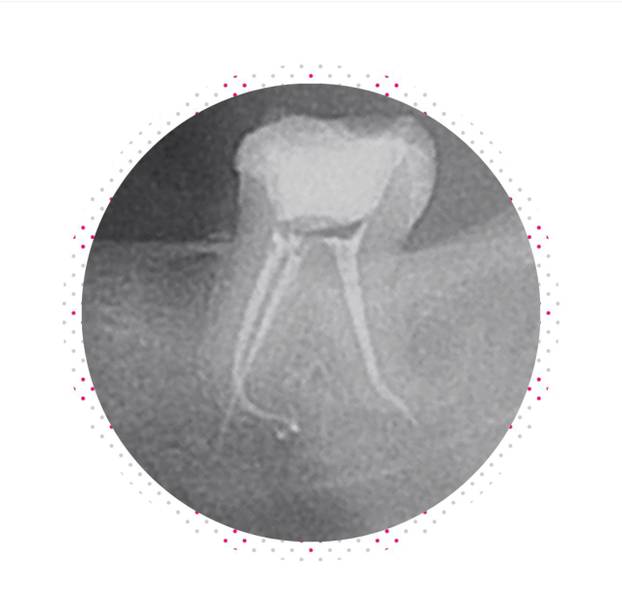

Dijagnostika započinje rendgenskim snimkama ili 3D CBCT-om, čime se precizno procjenjuju korijen, kanal i stanje kosti. Slijedi lokalna anestezija koja osigurava bezbolan zahvat.

Kada su upala i anatomija povoljni, provodi se jednoposjetno liječenje korijenskih kanala: kanali se u istom posjetu suše i hermetički pune toplinski omekšanom gutaperkom i biokeramičnim brtvilima. Takva metoda donosi više prednosti: manje dolazaka, brže smanjenje boli, manji rizik reinfekcije između posjeta i brži povratak funkciji.